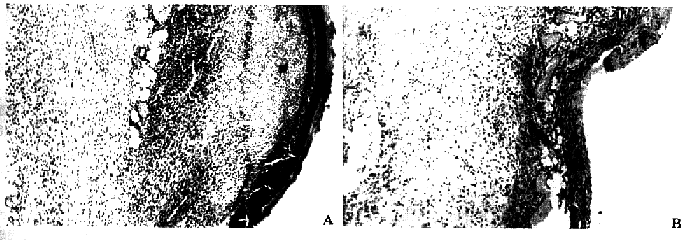

2.光镜观察:伤后3 d,未照射组伤口表面渗出非常明显,渗出物中有大量巨噬细胞和中性粒细胞,形成炎细胞“隔离带”,肉芽组织灶内成纤维细胞增生较活跃(图2A);而伤前2 d及伤后即刻照射组创面渗出物明显较少,尤以白细胞渗出减少为著,并有小灶状出血发生(图2B)。伤后3 d及7 d照射组情况与未照射组基本相同。

图2 致伤后不同时间创面的变化

伤后3天,未照射组创面内有大量渗出物,其中含大量巨噬细胞和中性粒细胞(A);伤后即刻照射组创面渗出物较少,有出血现象(B)HE染色×100